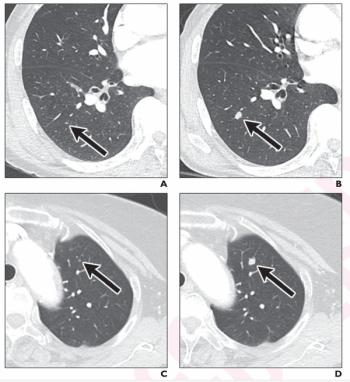

Emerging research shows that a multiple time-series deep learning model assessment of CT images provides 20 percent higher sensitivity than a delta radiomic model and 56 percent higher sensitivity than a clinical model for prognostic evaluation of ground-glass nodules.